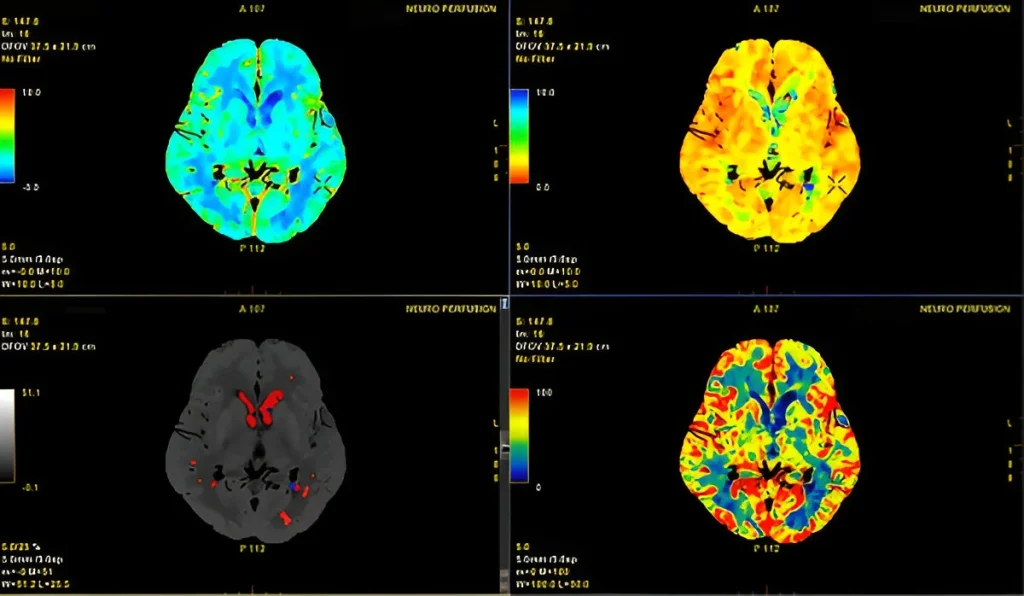

CT Perfusion Studies in Navi Mumbai | Henotic Diagnostics

At Henotic Diagnostics in Kharghar, we offer advanced CT Perfusion Studies that provide detailed insights into blood flow and brain function. Because this scan measures cerebral perfusion in real time, it helps doctors detect stroke, tumors, and vascular disorders early. In addition, our expert radiologists ensure accurate interpretation, so patients receive timely treatment. Moreover, we use state-of-the-art CT technology for safe, reliable results. Therefore, when you need CT Perfusion in Kharghar, choose Henotic Diagnostics for trusted care.